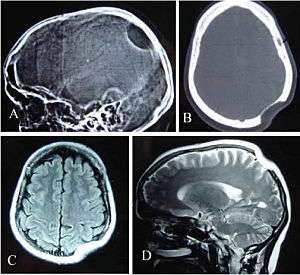

| Gorham's disease involving the left parietal bone: X-ray of the skull lateral view (A) showing a osteolytic area in left parietal region. CT scan bony window (B), MRI T1W Axial (C) and T2W Sagittal (D) revealing skull defect with normal brain parenchyma. | |